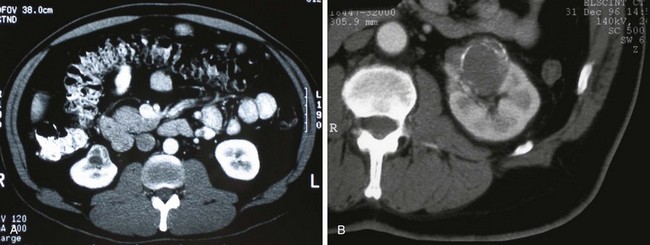

Category III lesions are more complex renal cysts that cannot be confidently distinguished from malignant neoplasms (Kausik, 2002; Israel and Bosniak, 2005). The radiographic features include thickened irregular or smooth walls or septa in which measurable enhancement can be observed (Fig. 49–7). In the absence of a mitigating factor such as renal trauma or infection, surgical exploration is usually indicated in healthy patients. About 50% of these lesions are malignant; the remainder prove to be benign multiloculated, hemorrhagic, or densely calcified cysts (see Table 49–2). Fine-needle aspiration of complex cysts is rarely performed because of concern about sampling error and tumor cell spillage.

Figure 49–7 Bosniak class III cysts. A, CT scan shows complex right renal cyst with thick and irregular septa and inhomogeneous character. B, CT scan shows somewhat thick-walled, complex left renal cyst also exhibiting irregular calcification and moderate heterogeneity.

(Courtesy of Dr. Terrence Demos, Maywood, IL.)